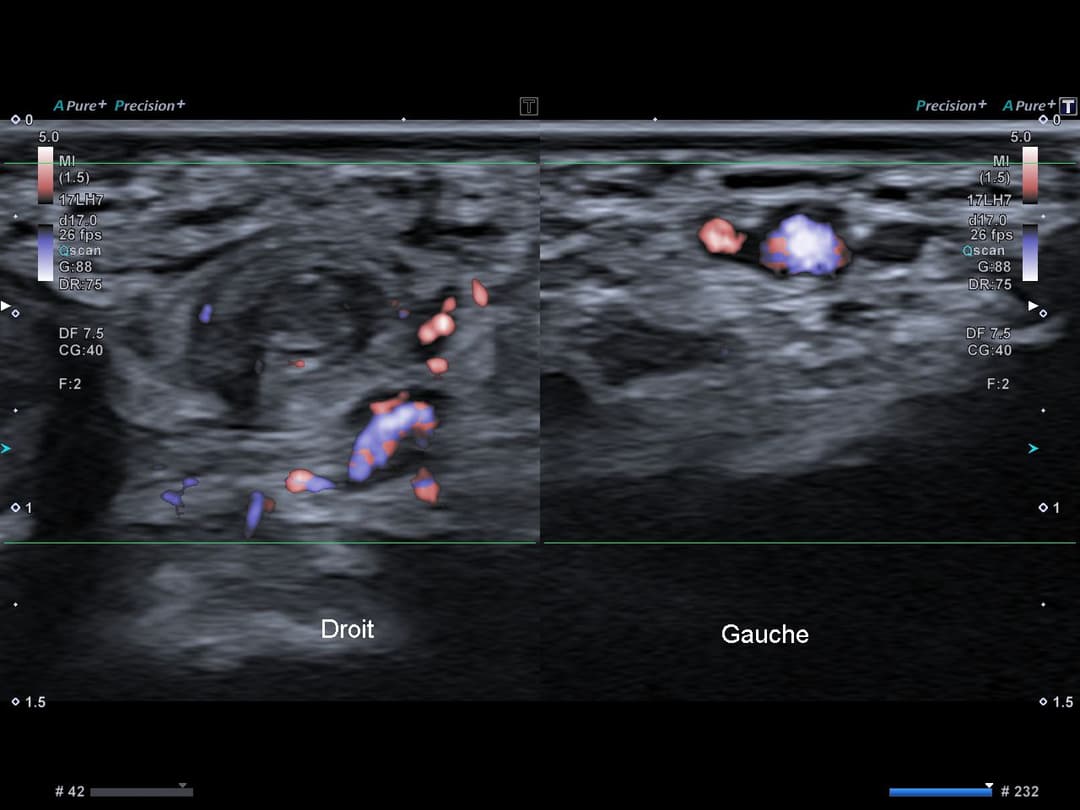

Comparatif avec le côté opposé non pathologique